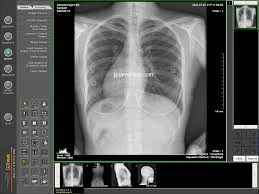

This program will enhance the doctor’s knowledge of radiology and imaging.  It will give the doctor a better understanding of imaging and the interpretation of imaging to enable him to better diagnose and treat his patients.

• Case Studies which you will help interpret during the class!

You will leave this class with a better understanding of what you are looking for and the importance of recognizing abnormalities presented.